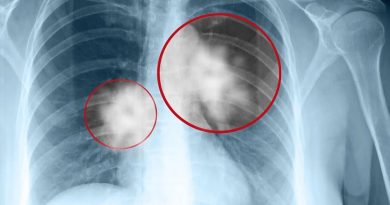

Mihai Leu a fost diagnosticat, în 2015, cu cancer la colon, dar după patru operații, a învins boala, așa cum a făcut cu adversarii din ring și cu cei de la curse.